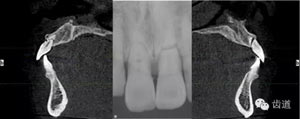

術(shù)前放射片

放射檢查:11,21根中三分之一至根尖三分之一處折斷。

本病例為前牙外傷致根折,牙周無(wú)明顯炎癥,唇側(cè)骨板厚度大于1mm且根方骨量充足,適合即刻種植。術(shù)前簡(jiǎn)易導(dǎo)板的制作以及術(shù)中牙周探針精確的測(cè)量,保證了種植體的三維位置及軸向均按標(biāo)準(zhǔn)的即刻種植手術(shù)進(jìn)行。術(shù)后參考拔除牙齒的頸部形態(tài)制作個(gè)性化愈合基臺(tái),實(shí)現(xiàn)了對(duì)牙齦塑型的早期干預(yù),打破了傳統(tǒng)二期牙齦成型的做法,所成型的牙齦袖口與之前的天然牙相似,有利于維持牙齦形態(tài)的穩(wěn)定和美觀。